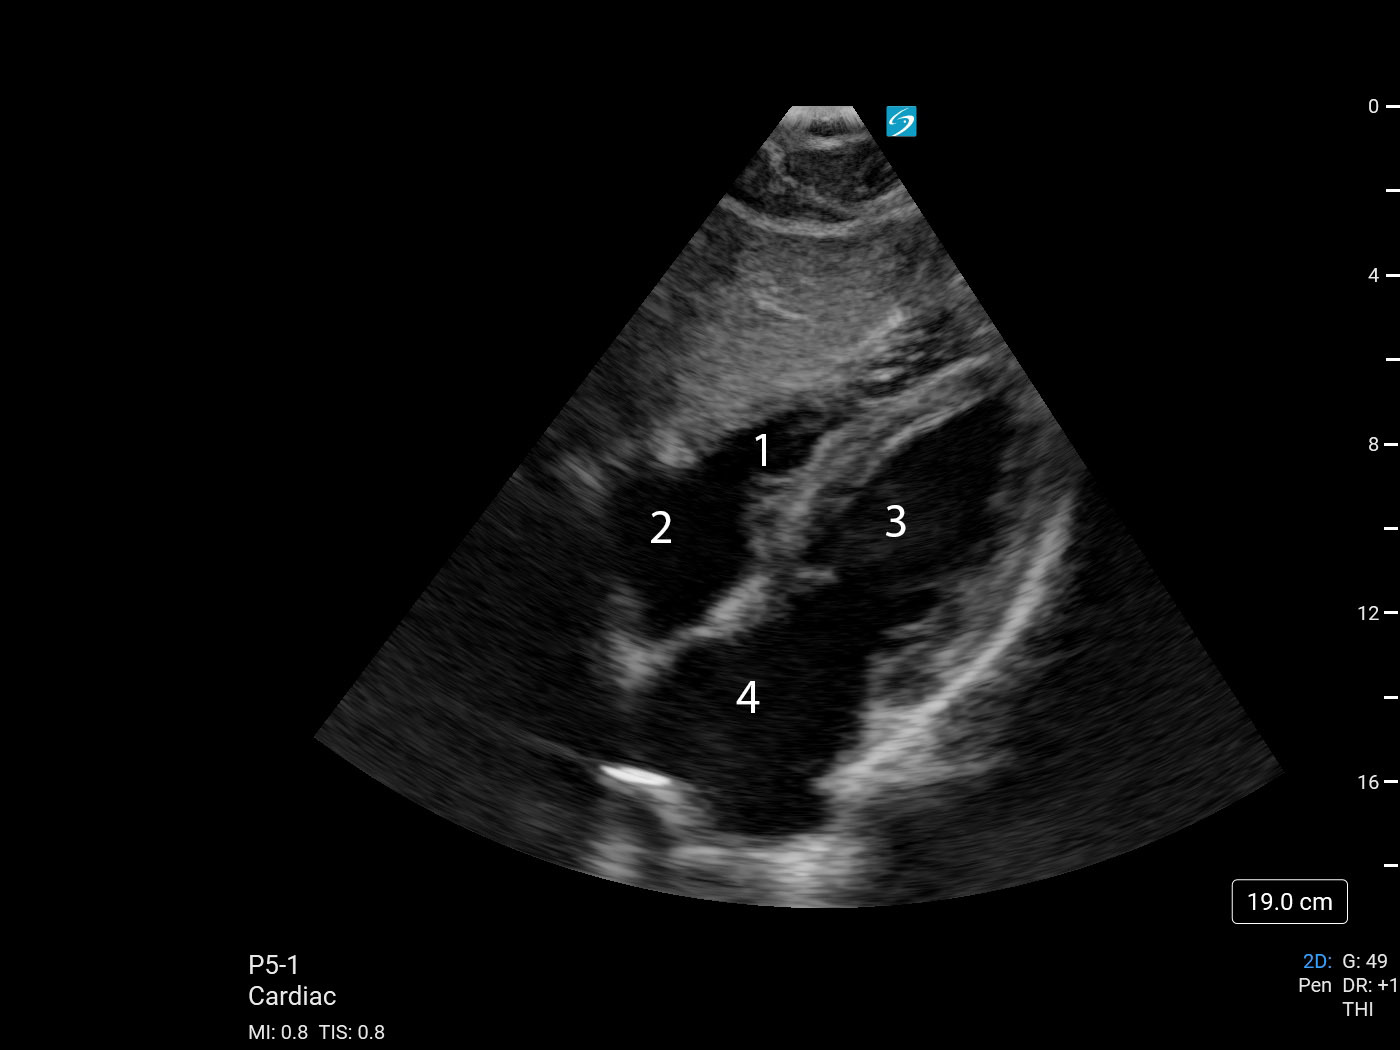

Bild 1: Herz, subkostaler 4-Kammerblick (mit blauem Punkt)

1. Rechter Ventrikel (RV)

2. Rechtes Atrium (RA)

3. Linker Ventrikel (LV)

4. Linkes Atrium (LA)